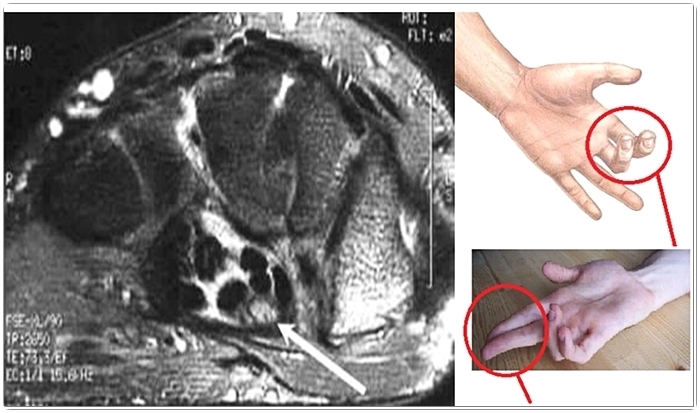

손 저림으로 가장 흔히 볼 수 있는 질환이 손목 터널 증후군입니다.

그럼 무엇이 문제가 되어 이렇게 저림이 나타나는 것일까요?일단 손의 구조를 확인해보도록 하겠습니다. 현재 손목에는 손가락을 향하고 있는 9개의 힘줄 이외에 1개의 신경이 있습니다.이 모든 것은 손목에 있는 특정 터널을 지나고 있습니다.

해당 손목 터널에 어떤 이유로 신경이 눌리게 되고 이런 증상이 생기는 거예요.결과적으로는 신경이 눌리는 것으로 인해서 손가락 이외의 손가락이 아프거나 저리거나 하는 증상이 나타납니다.

자가진단방법은 이상 확인에 도움이 되지만, 보다 정확한 내용은 내원을 통해 확인하시기 바랍니다.먼저 손목을 가볍게 두드려 보면 따끔따끔할 수도 있고, 반대로 무감각해질 수도 있습니다. 이런 이상 증상들을 확인해야 해요.

또한 손목을 구부려 봐도 알 수 있고, 1분이라는 시간 동안 머리 위에 유지하는 것도 있습니다.

이 때 통증이나 무감각이 일어날 수 있으며, 따끔거릴 때는 의심해 보기도 합니다. 다만, 앞에 말씀드린 것과 같이 보다 자세한 내용은 전문의를 통해 확인해 볼 필요가 있으며, 가급적 스스로 판단하는 일이 없기를 바랍니다.